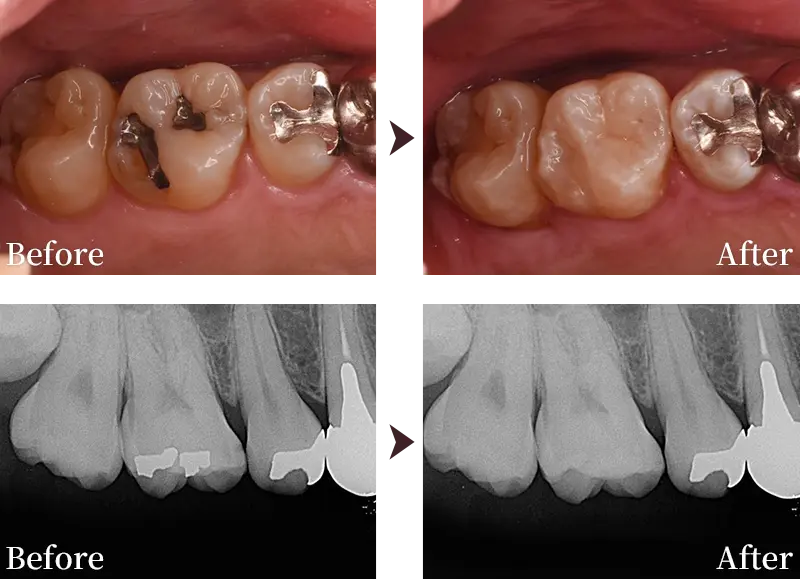

症例紹介2

症例2

主訴 銀歯を白くしたい

治療内容 右上5番、6番のダイレクトボンディング

治療回数 1回

標準費用(自費) 12万円(税込)

リスク・副作用

• 経年劣化により変色や破損する場合があります。

• 治療後、歯がしみたり違和感が出る可能性があります。